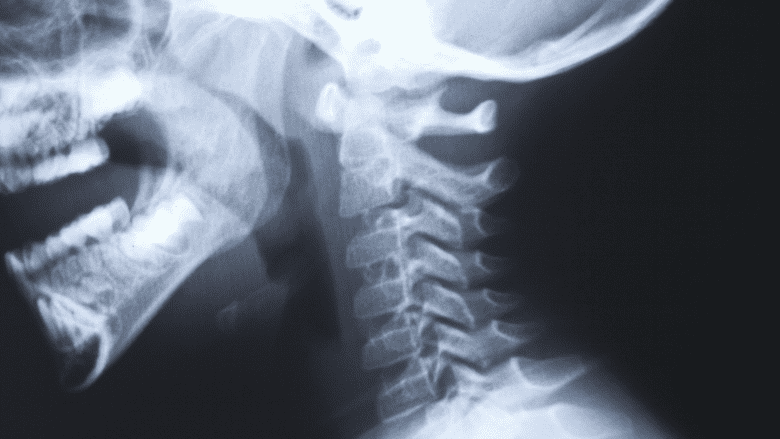

During the post-surgery visits, x-rays are taken to evaluate the progress of healing.

There are usually at least 2 follow-up appointments where x-rays are taken of the cervical spine to see how the healing is progressing. For example, x-rays might be taken within a few days or weeks after surgery, and then again at 3 months. These x-rays help to check that the bones look healthy and the artificial disc has not migrated out of position. Multiple x-rays are taken, including with the cervical spine in flexion and extension to test the artificial disc’s full range of motion. Beyond the 3-month point, x-rays are taken either on a yearly basis or if there are new symptoms, such as pain.